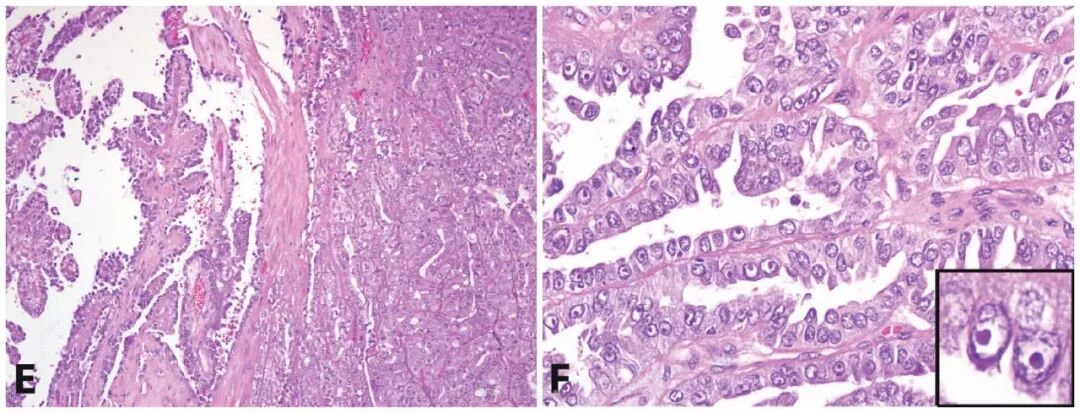

最近一项对9例FH胚系突变患者肾肿瘤的分析中,仅1/3具有乳头状结构。这类肿瘤中的纤维脉管轴心常水肿或玻璃样变,常见微乳头状结构。所有肿瘤均为多种结构混合,如管状乳头状、实性、囊性(常伴囊内乳头状或管状乳头状结构)。常见与集合管癌的形态学重叠,且促纤维结缔组织增生的间质中伴浸润性癌及炎症。HLRCC相关肾细胞癌的管状囊性区有时可见显著核仁。

5. HLRCC综合征相关肾细胞癌中,部分病例表现为乳头状及实性生长,形似实性乳头状肾细胞癌;但细胞学上具有显著包涵体样核仁、伴显著染色质边集。

6. 部分HLRCC综合征相关肾细胞癌可能会类似集合管癌,肿瘤性小管呈浸润性生长;但FH表达缺失、正常肾脏组织FH表达阳性(插图),证实为HLRCC综合征相关肾细胞癌。